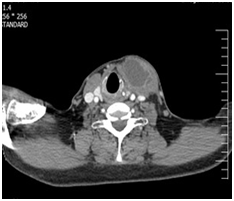

A 56-year-old male, smoker, with no significant past medical history, presented with a 18-weeks history of a nodular swelling of the neck. The patient also reported dry cough without fever for the past year. There was no history of weight loss, anorexia or asthenia. Physical examination revealed a 6cm cystic nodular mass in the left - anterior neck which seemed to be in the left lobe of thyroid gland. The throat was normal. Body temperature was 37°C, the heart rate was 92/min, and blood pressure was 149/80mm Hg. Enlarged lymph nodes were not palpable in rest of body. Chest- X-ray examination was normal. Thyroid function tests were in the normal range. WBC: 7000/mm3 with a normal differential count, haematocrit: 38%, haemoglobin: 12.7g/dl, platelets: 424.000/mm3. Erythrocyte sedimentation rate was 12mm in the first hour and the C reactive protein (CRP) was 3.4mg/l (normal value <5mg/l). The liver functions tests were normal. Ultrasonography and CT-scan of the neck revealed that the left lobe of the thyroid gland contained many thick fluid material with cystic changes resulting in an enlargement of the left lobe gland (Figure 1). The rest of the gland had a normal echogenicity and regular margins. The chest X-ray was normal. Tuberculin test was negative. ultrasound guided fine-needle aspiration was performed, AFB in aspirated pus by Ziehl Nelsen stain was negative. The specimen submitted for culture, bacterial and tuberculosis was negative too. Sulfure- granule for actinomycosis was negative. The patient had surgery, which yellow pus aspirated (Figure 2). Resection of the left lobe and istem was performed, the rest of the gland showing no abnormality. On gross examination, the specimen was necrotic and debris tissue (Figure 3). Microscopic examination revealed necrotizing epithelioid granulomas with Langhans’ giant cells (Figure 4). The diagnosis of thyroid tuberculosis was therefore made. Acid fast bacilli (AFB) were absent in the sputum. Abdominal ultrasonography revealed no lymph node enlargement. The patient was placed on isoniazid (300mg per day), rifampicin (600mg per day), ethambutol (1200mg per day) and pyrazinamid (1500mg per day) for 2months and isoniazid and rifampicin for the subsequent 4months. The clinical outcome was good. Ultrasonography of the neck and of the abdomen at 8months of antituberculous treatment revealed no abnormality of the thyroid gland. The enlarged lymph nodes of the jugular and carotid chains were not present.Thyroid functions test (T4, T3 and TSH) was normal.

Figure 1 CT-scan of neck show a cystic lesion in thyroid.

A 72-year-old man presented with history of left thyroid lobe swelling for 5-7month, which was gradually increasing in size with no compressive of neck structure or any associated symptoms. On physical examination, he had a left thyroid cystic and solid nodule.The nodule was no tender and moving with swallowing. Lymph node was not palpable in the neck. The systemic examination was normal, clinically he was euthyroid. Ultrasound of thyroid showed a left sided show cystic and solid nodule. CT-scan of neck with IV contrast shows a solid and cystic mass with peripheral vascularity. The right lobe was normal in size with few small solid and cystic nodules (Figure 5). Her chest X-ray was normal. His CRP, ESR and complete blood count and routine biochemistry were normal.FNA of left thyroid lobe in two time was performed which showed pus material. Cytology revealed follicular lesion. AFB in aspirated pus by Ziehl Nelsen stain was negative. Culture for bacterial and tuberculosis was negative too. He underwent left lobectomy and istmectomy, and her histopathology report showed granulomatous inflammation in the left lobe. With pathologic finding of chronic granulomatous inflammation along with necrosis and with possibility of tuberculosis in the left lobe (Figure 6), he was started on antituberclusis treatment with four drug regimen for the first 2months followed by three drugs regimen for the next 4months along with. He completed her treatment and in follow-up remained asymptomatic.T4, T3 and TSH was in normal range.

Figure 5 CT-scan of neck show a cystic lesion in thyroid.